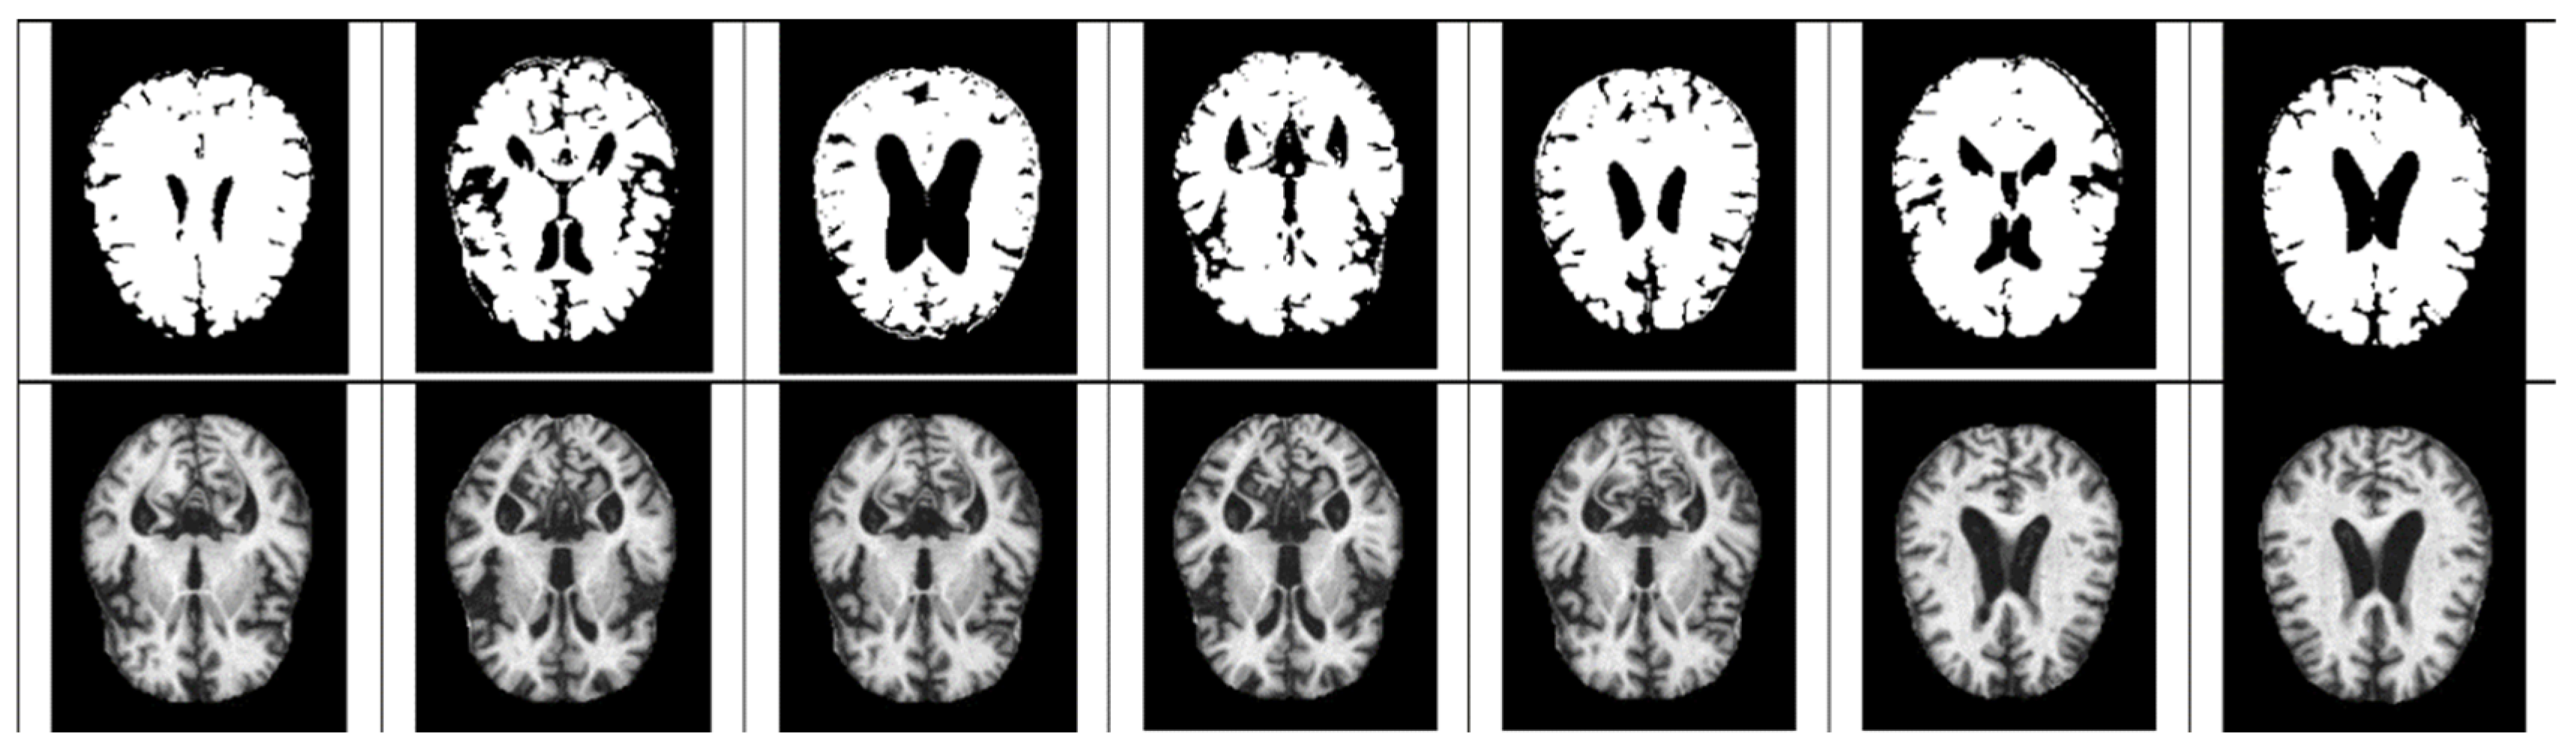

- As mentioned above, the method of diagnosing AD on MRI images compares the size of the hippocampus. However, due to the nature of the existing CNN model, it is difficult to detect because it is not sensitive to image dispersion. Therefore, additional processing of the color space of the image is required.

- For Z-score normalization, the interval to which each pixel belongs is converted to [−1, 1], and for min–max, it is converted to [0, 1]. During the computation of the convolutional neural network, the pixel intensity of [0, 255] is adjusted for fast convergence and accurate feature extraction.

- The size space of pixels constituting the Alzheimer’s MRI data set is [0, 255]. Among them, patients with AD with reduced hippocampus will have more pixels close to zero than normal people. On the premise of this, the average value of pixel intensities in each MRI image is set as a threshold value. Alzheimer’s should recognize changes in size contraction rather than changes in brain function. Based on this information, it is necessary to set the space as an important feature for the color information of MRI rather than a feature representing the shape of the brain.